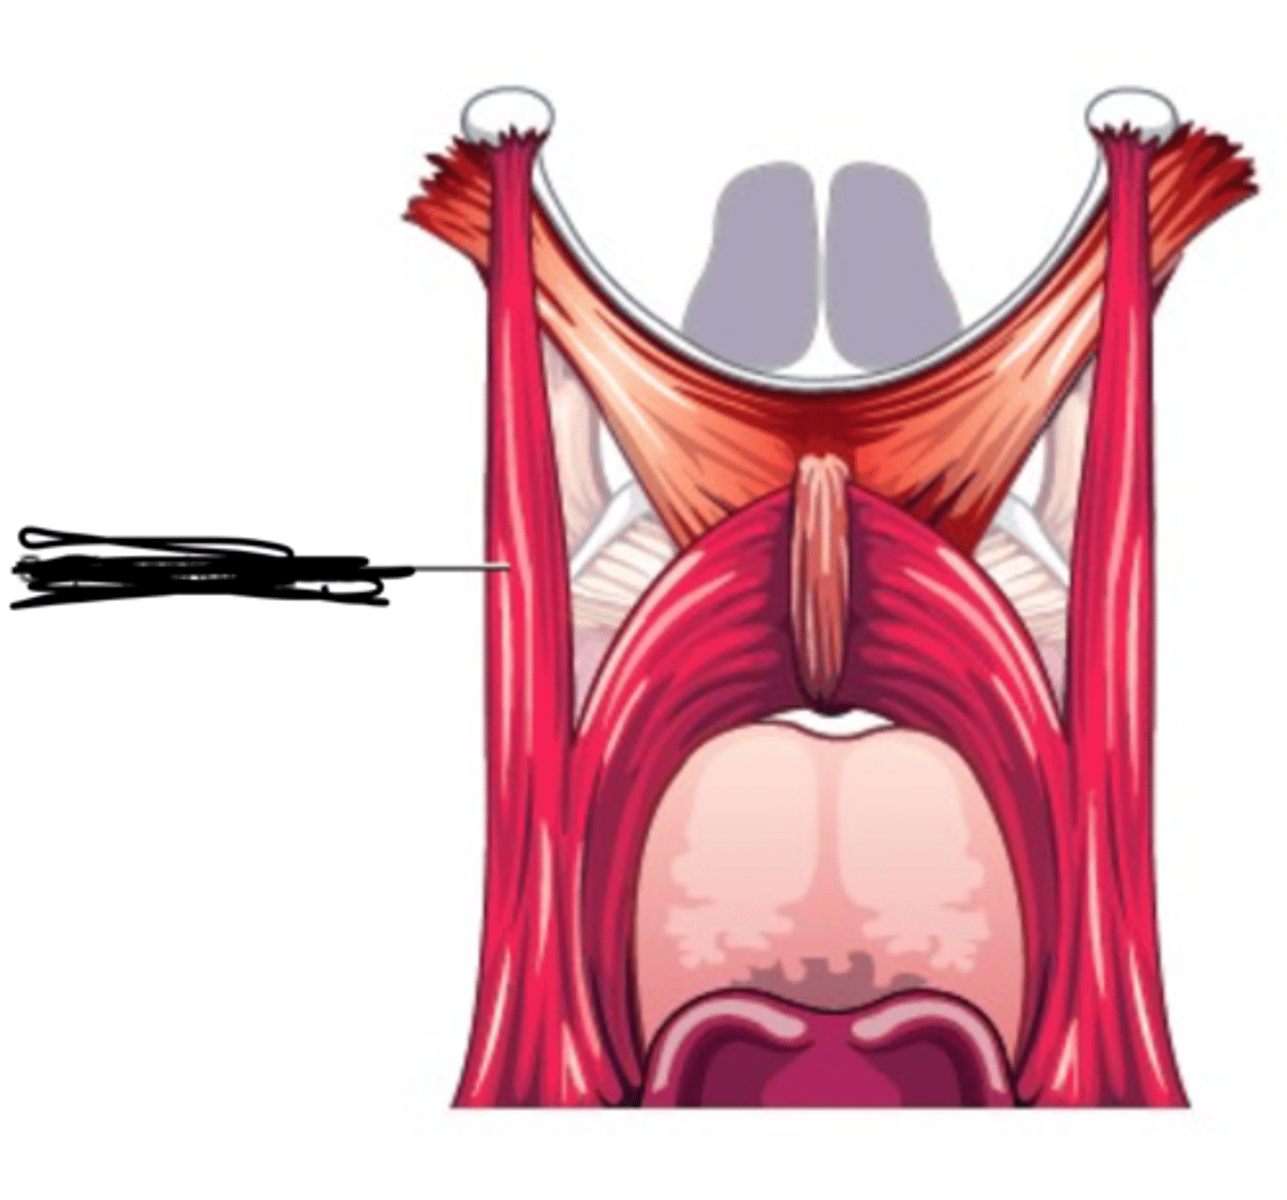

Stylopharyngeus Figure

Stylopharyngeus Description

Long thin muscle

Origin - styloid process of temporal bone

Course - inferior, entering between

superior and middle constrictor

Insertion - blend with constrictors, with

some fibers inserting on thyroid cartilage

Action - elevate and dilate pharynx